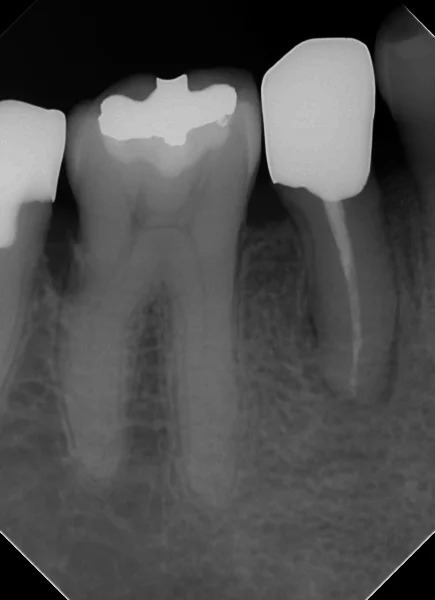

そして、1年半経過後、経過のレントゲンを撮らせて頂きました。

閉鎖根管の治療には根気が必要|坂寄歯科医院(取手市藤代) - 画像4

根の先の膿が随分と無くなってきているのが分かるかと思います。

処置開始~神経の治療完了時(RCF時)~1年半経過後を並べるとこうなります。

こうみると随分と良くなっているのが分かるかと思います。

それでもうっすら根の先の骨には空洞が残っていますね。

違和感や食事時の痛みなどは出ていませんので、特に問題はありませんが・・・

骨が完全に治るのには恐らくあと1年ほどは掛かりそうですね・・・。